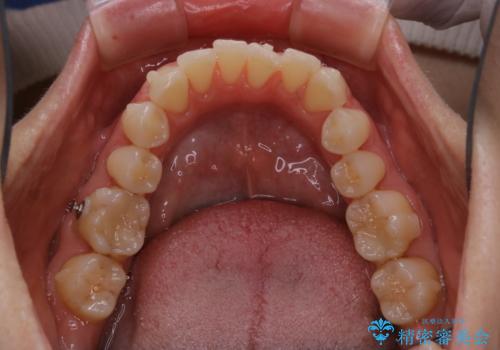

- インビザライン矯正治療中にステインが気になるとのことで来院されました。全体的にステインが付着していたため自費クリーニングPMTC(60分コース)を行いました。

インビザライン矯正治療中は、ご自身の歯にアタッチメントという突起物(効率的に歯の移動を行うため)をつけます。そのため、通常時よりもステインが付きやすい状態になることがあります。

インビザラインは透明なマウスピースなので、ご自身の歯にステインなどが付着していると、見た目に影響してしまうことがあります。

矯正治療中の虫歯・歯周病・口臭予防としても、定期的にPMTCを行うことが大切です。